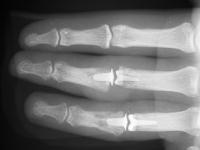

These are before and after radiographs of middle and ring proximal interphalangeal joints in a young man after a rotating blade injury resulting in dorsal bone and soft tissue loss. Initially treated elsewhere with K wire fixation, ring finger skin graft and abdominal flap reconstruction of the middle finger, he presented with instability, stiffness, pain and lateral angulation. Surgery was technically difficult because normal landmarks were distorted or missig. Despite complex bone and soft tissue loss,  stability was rendered in part by the restoration of concentric joint surfaces.

Anteroposterior views:

Correction of lateral deviation.